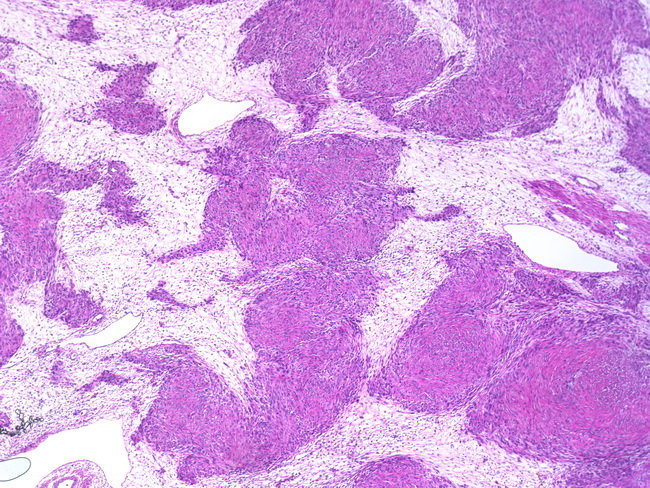

Myxoid Leiomyosarcoma. A, The Tumor Has An Infiltrative Growth Pattern

leiomyosarcoma myxoid tumor infiltrative growth leiomyoma necrosis tumors myometrium hypocellular abundant uterus eosin minimal atypia hematoxylin magnifications